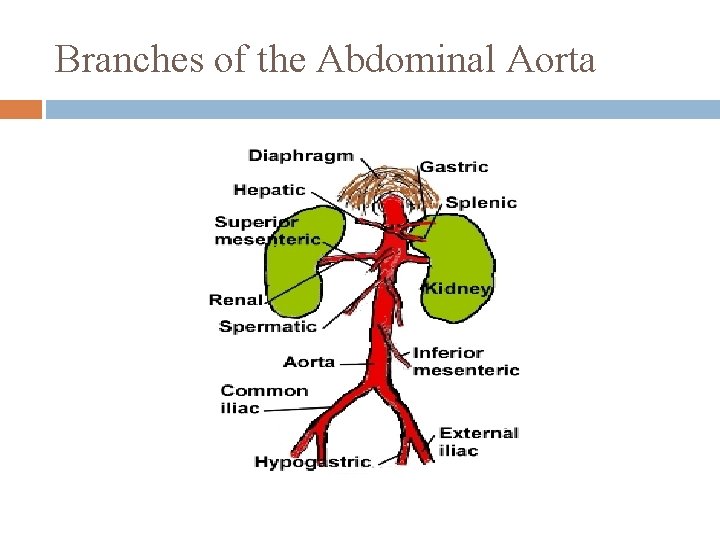

Branches of the Abdominal Aorta 1. descends slightly to the left of the vertebral column retroperitoneal Branches: Celiac Trunk (3 branches) � � � Lt gastric artery: stomach Splenic artery: spleen: stomach, & pancreas Common Hepatic Artery: liver, stomach, gallbladder, & duodenum

Branches of the Abdominal Aorta 2. Superior Mesenteric Artery: pancreas, duodenum, small intestines, most of large intestines 3. Inferior mesenteric Artery: terminal portion of the colon, sigmoid colon, & rectum

Branches of the Abdominal Aorta

5 Paired Arteries from Abdominal Aorta 1. Inferior phrenic arteries � 2. Suprarenal arteries � 3. kidneys Gonadal arteries � 5. Adrenal glands Renal arteries � 4. inferior surface of diaphragm Testicular or Ovarian Lumbar arteries � vertebrae, spinal cord, abdominal wall